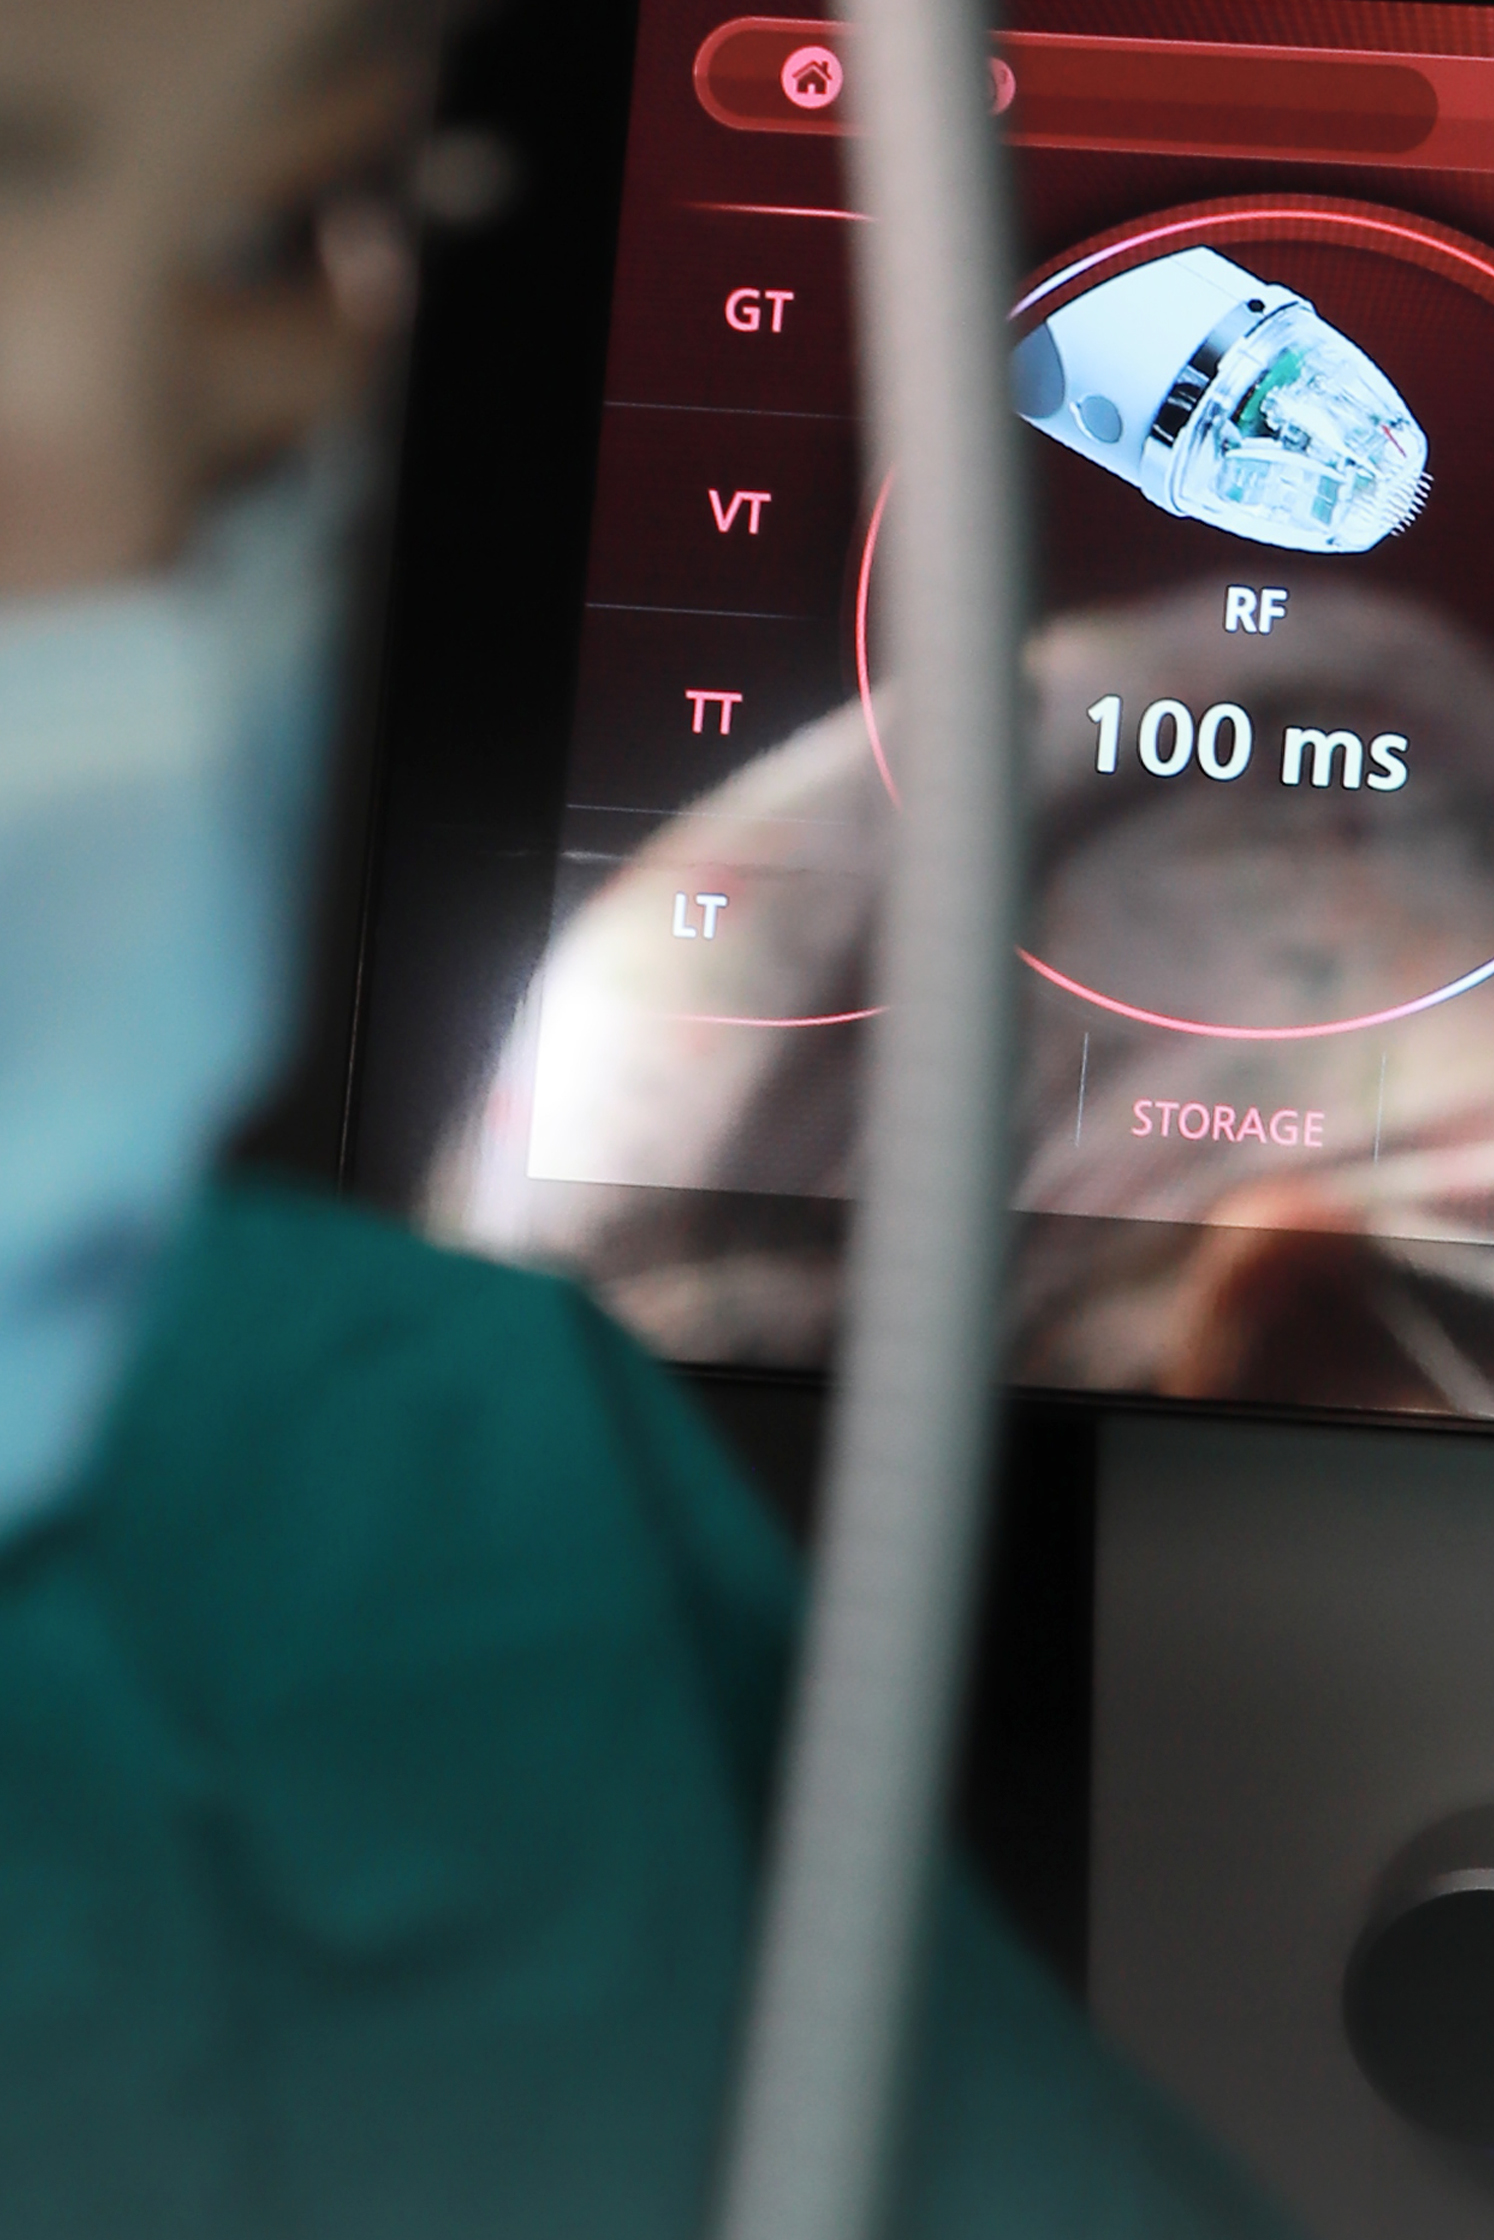

논현산부인과 헤스티아 여성의원 신사본점에 내원하시면 정확한 진단을 위한 요역동학검사를 추천드리고 있습니다. 헤스티아 여성의원 신사본점에서는 검사 기계가 마련되어 있기 때문에 요역동학검사가 가능합니다. 검사 후 맞춤형 치료를 통해 요실금을 효과적으로 개선하실 수 있었어요. 만약 복압성 요실금으로 수술을 진행하게 된다면 헤스티아 여성의원 신사본점의 수술법과 리뷰를 체크해 보시길 바랍니다. 헤스티아 여성의원 신사본점은 TOT 수술로 요도 괄약근을 받쳐 올려주기 때문에 복압에 견딜 수 있게 되며 증상 재발을 막아주는 효과가 있어요.

TOT 수술은 같은 수술이어도 증상 개선 정도가 병원마다 차이가 나게 돼요. 헤스티아 여성의원 신사본점은 요실금 수술 건수도 상당하며 의료진의 수술 노하우가 매우 풍부합니다. 요도를 지지해 주는 테이프를 삽입하고 수술 부위에 잘 고정시켜주고 있어서 요실금 증상이 재발하는 것에 대해 방지 효과가 높고 수술 부위에 부작용이 생길 확률도 매우 낮습니다.